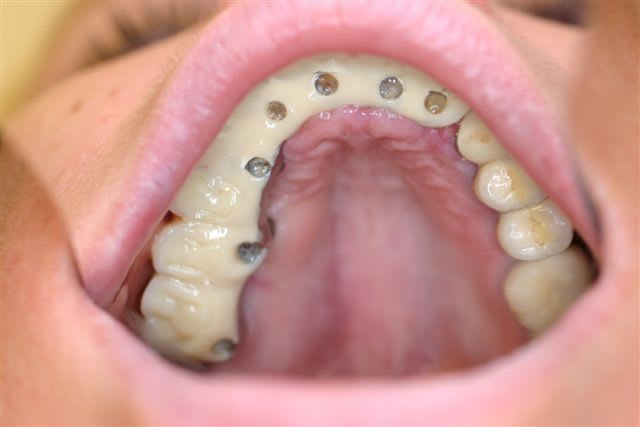

Perte d un greffon iliaque

Retraité en basale voici 6 ans avec succès